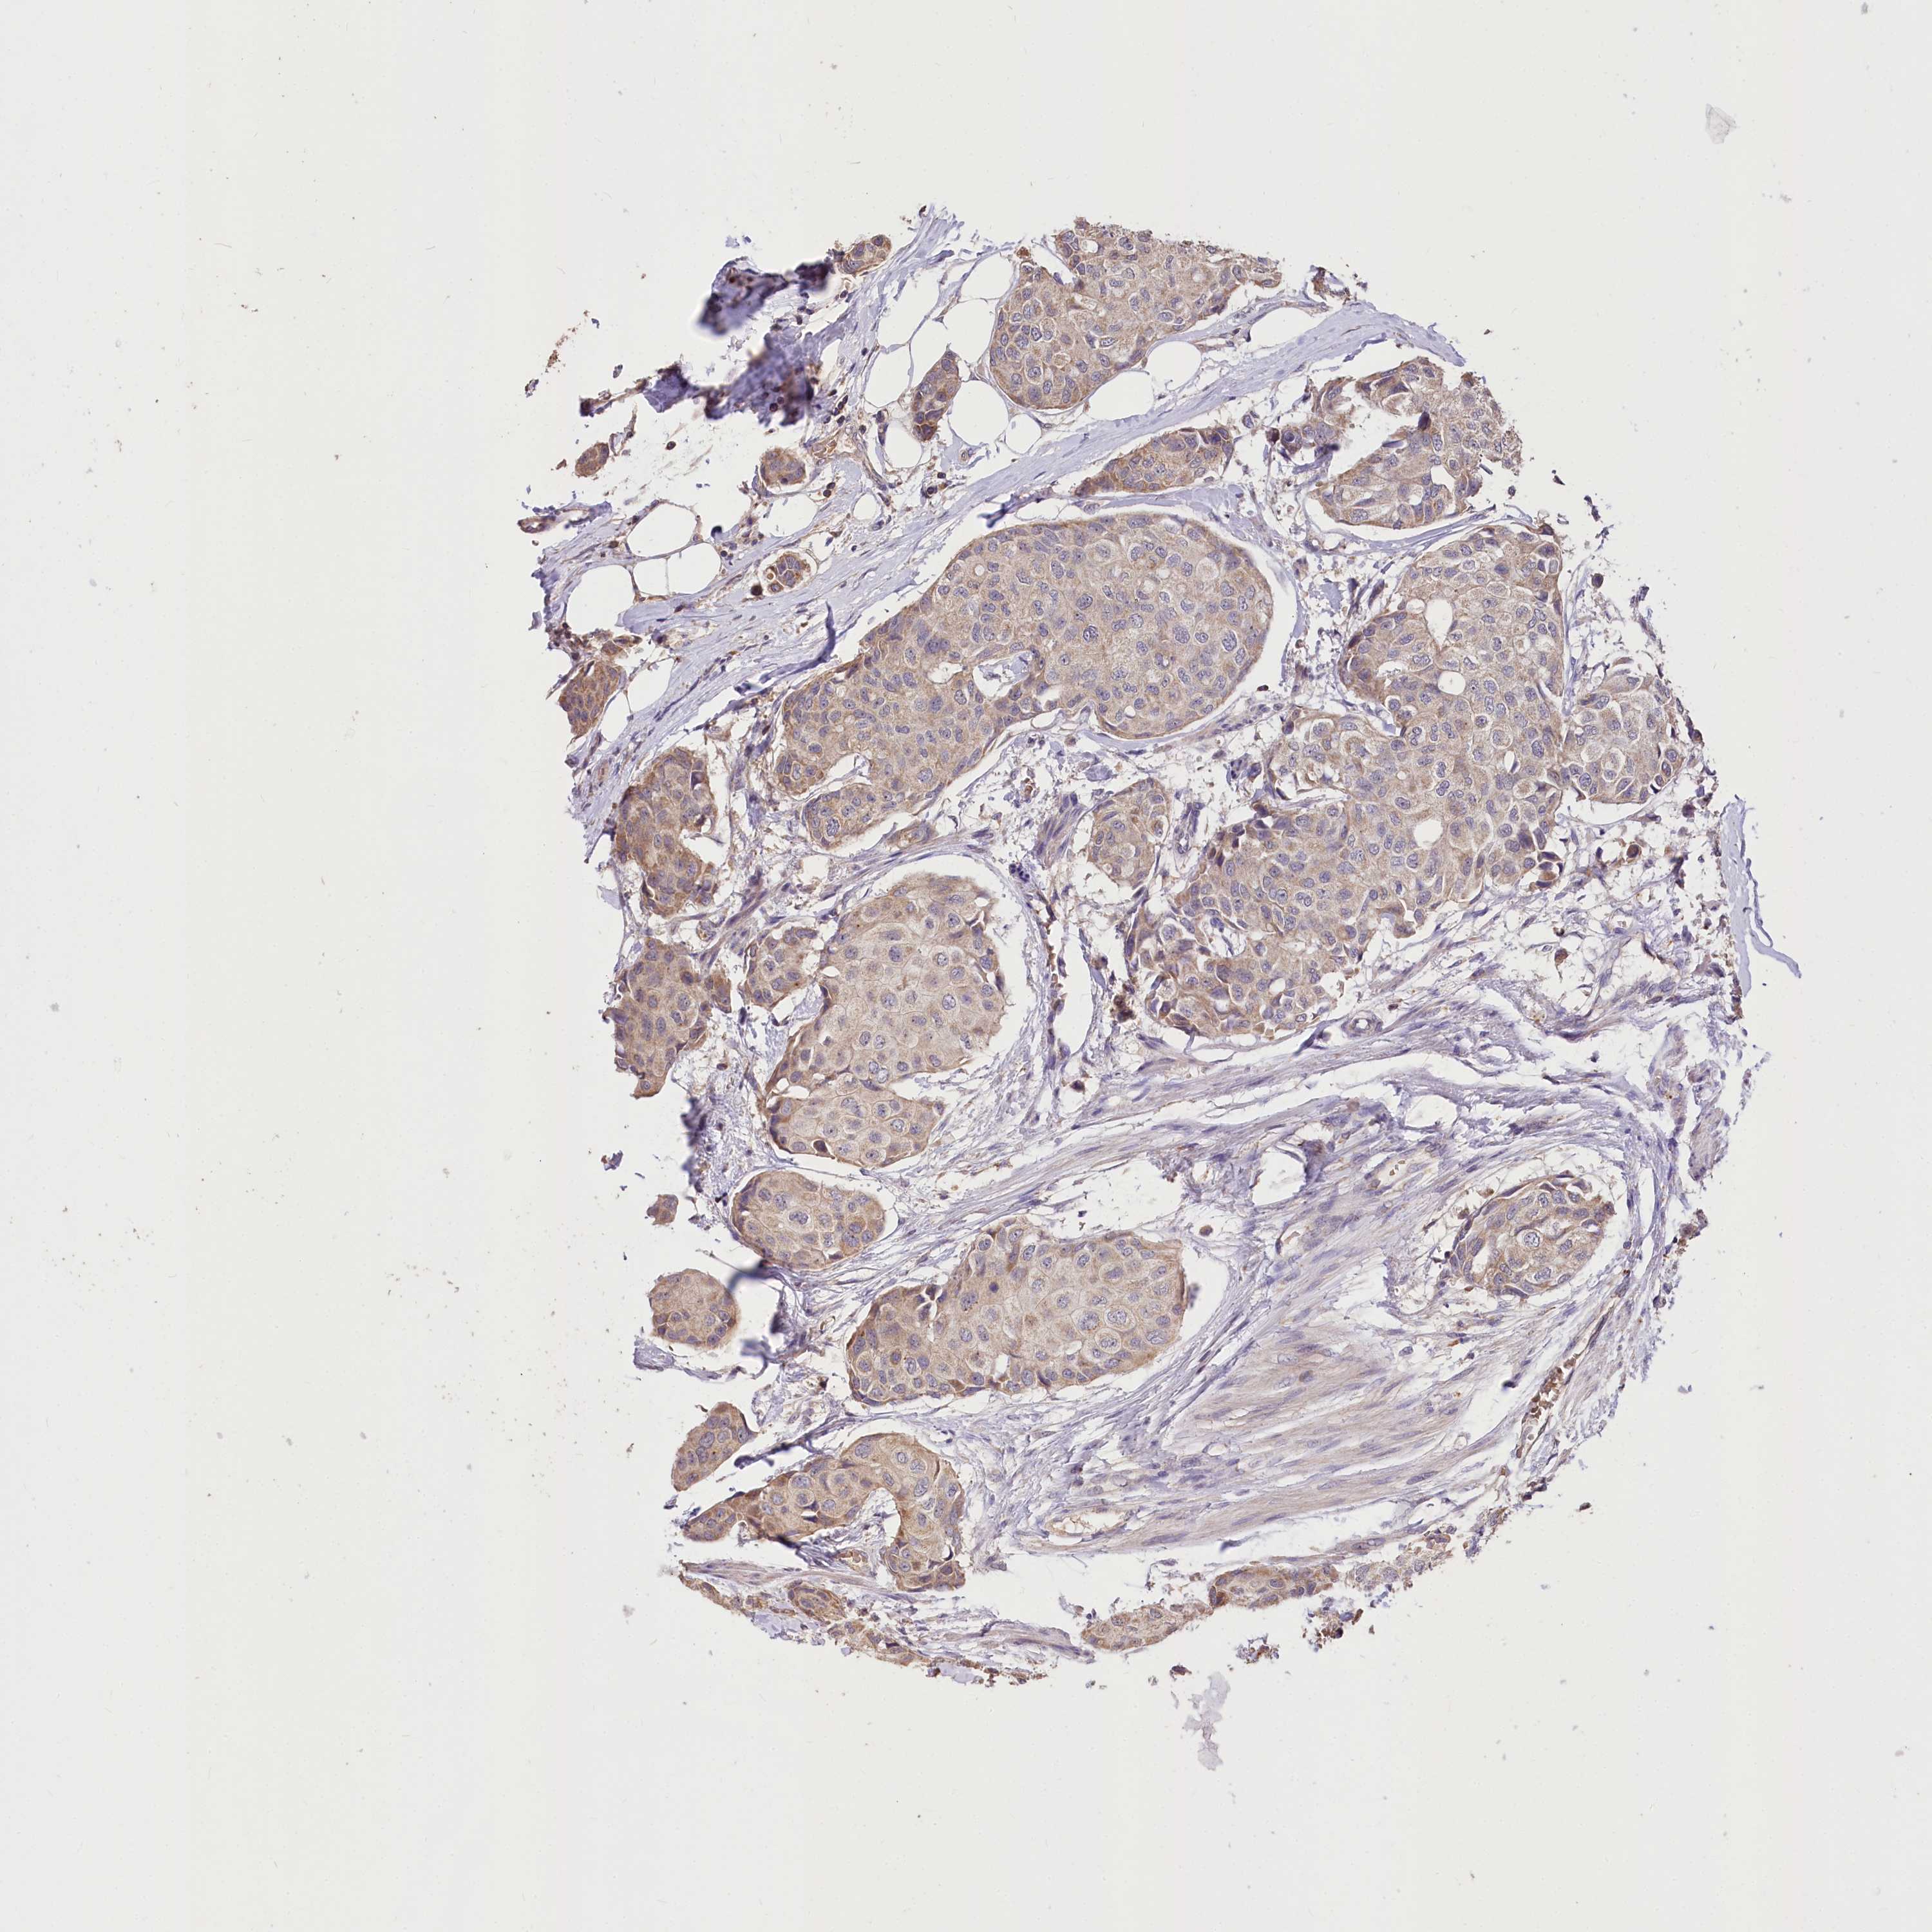

CANCER BREAST CANCER Show tissue menu

BRCA TCGA BRCA VALIDATION PROTEIN EXPRESSION

Breast cancer

Human cancer